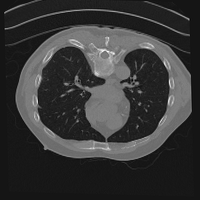

Exp. 3: Adult thorax data: To show the versatility of our approach we also apply it to adult thorax scans. For this experiment no organ specific training is performed but the whole volume is used. We evaluate reconstruction performance similar to Exp. 1 and Ti^^subscript𝑇𝑖\hat{T_{i}} prediction performance when ΩΩ\Omega is projected on an external plane, comparable to X-Ray examination using C-Arms. The latter provides insights about our method’s performance when applied to interventional settings in contrast to motion compensation problems. 60 healthy adult thorax scans were randomly selected, 51 scans used for ΩtrainsubscriptΩ𝑡𝑟𝑎𝑖𝑛\Omega_{train} and nine scans used for ΩvalidationsubscriptΩ𝑣𝑎𝑙𝑖𝑑𝑎𝑡𝑖𝑜𝑛\Omega_{validation}. Each scan is intensity normalised and resampled in a volume of 200×200×200200200200200\times 200\times 200 with spacing 1mm×1mm×1mm1𝑚𝑚1𝑚𝑚1𝑚𝑚1mm\times 1mm\times 1mm. Using the Fibonacci sampling method, 25 sampling plane of size 200×200200200200\times 200, evenly spaced between -50 and +50, were rotated over 500 normals. Training took approximately 20 hours for 60 epochs. Fig. 4c shows an example reconstruction result gaining 28dB PSNR with additional SVR. Ti^^subscript𝑇𝑖\hat{T_{i}} prediction takes approx. 20 ms/slice for this data.

Refer to caption

(a)

(b)

(c)

(d)

(e)

(f)

Figure 4: (a): Comparison of a single slice from raw low-dose thorax CT data; (b): reconstruction based on SVRNet Ti^^subscript𝑇𝑖\hat{T_{i}} regression; (c): SVR initialized with SVRNet transformations after four iterations of SVR; (d): PSNR of (b) and (c) compared to (a). (e): shows a projection of an unseen pathological test CT volume as DRR and (e) shows a DRR at the location predicted by our method when presented with the image data in (e).